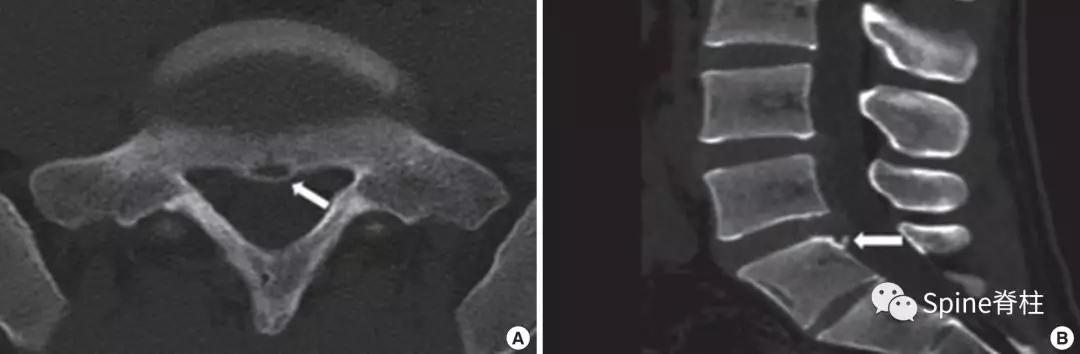

图:15岁腰痛男孩,左侧腰5椎弓根裂

A:T1左侧腰5椎弓根低信号(箭头);B:T2左侧腰5椎弓根高信号(箭头);C:T2轴位左侧腰5椎弓根骨折线明显,伴高信号区(箭头)。

- 椎板裂病例

图:17岁腰痛男孩,L5双侧峡部裂和右侧椎板裂

C:右侧椎板增厚,不连续